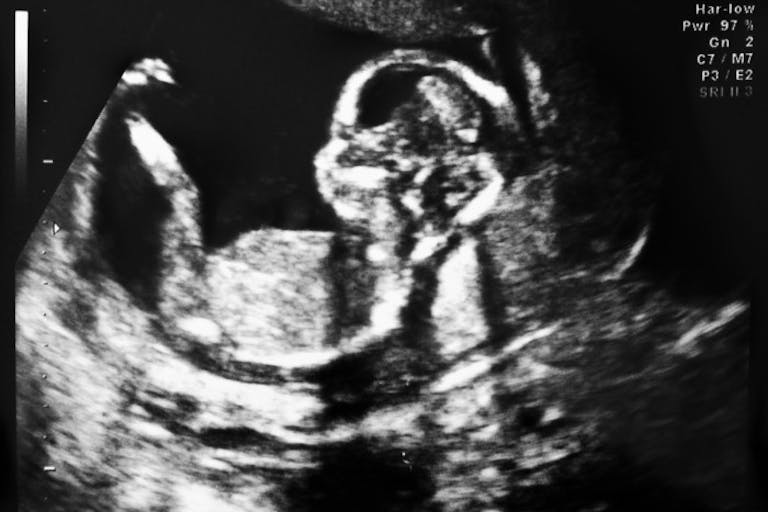

At eleven weeks, the baby is fully formed, with arms, legs, fingers, and toes. His heart is beating, and he breathes amniotic fluid. If the baby is female, she has a womb and ovaries of her own.